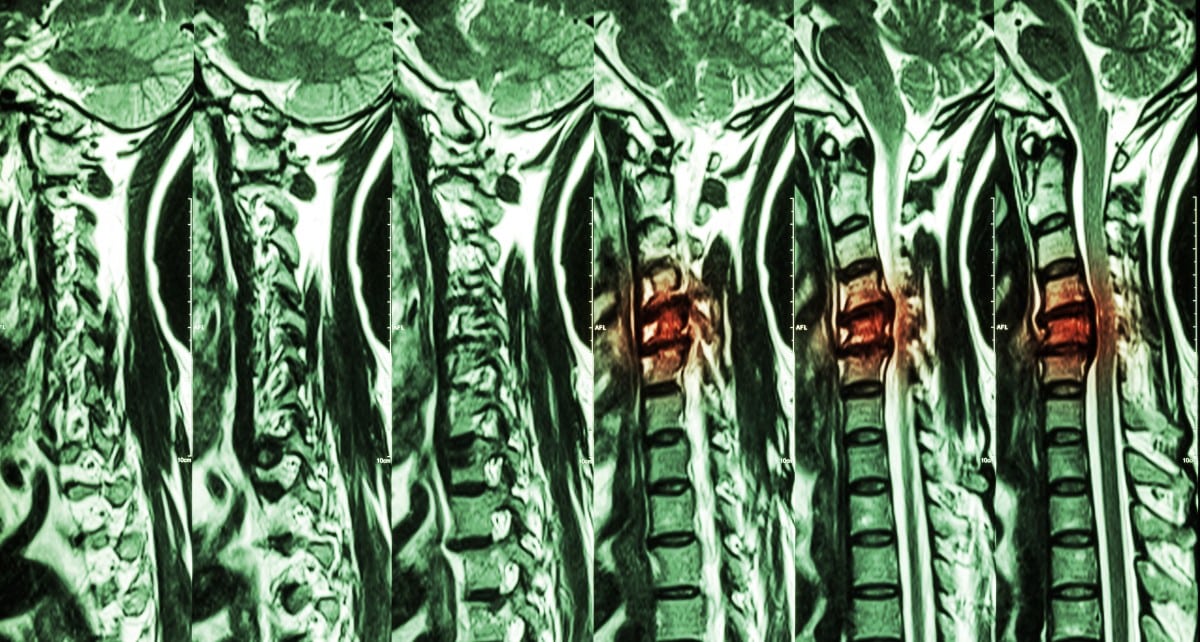

Acute Spinal Cord Compression NEJM Spinal Cord Compression Recovery Advances in stem cell research and nerve cell regeneration give hope for greater recovery for people with spinal cord injuries. This article will focus on atraumatic causes of spinal cord compression, including degenerative spondylosis with myelopathy, metastatic disease of the. The immediate treatment for spinal cord injury is directed at reducing the permanent impact of the injury. The early stages. Spinal Cord Compression Recovery.